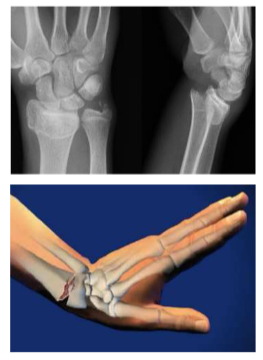

<p>What was the mechanism of injury for this x-ray?</p>

What was the mechanism of injury for this x-ray?

FOOSH - fall on outstretched hand

Colles Fx

• distal radius fx

• brachioradialis - distal radius attachment, pronation/supination

• may require plates and screws if dislocated

• acute - cast above the elbow and below the elbow

<ul><li><p>distal radius fx </p></li><li><p>brachioradialis - distal radius attachment, pronation/supination&nbsp;</p></li><li><p>may require plates and screws if dislocated&nbsp;</p></li><li><p>acute - cast above the elbow and below the elbow&nbsp;</p></li></ul><p></p>

Wrist Fx

Scaphoid - snuff box pain

• immobilize thumbs, fingers, and wrists up to the elbow

• controls pronation/supination

• carpal row neutral?

Fracture Orthosis with palmar extension aligned with wrist a 0 degrees extension - not a functional position

<p>Scaphoid - snuff box pain </p><ul><li><p>immobilize thumbs, fingers, and wrists up to the elbow&nbsp;</p></li><li><p>controls pronation/supination</p></li><li><p>carpal row neutral?&nbsp;</p></li></ul><p></p><p>Fracture Orthosis with palmar extension aligned with wrist a 0 degrees extension - not a functional position&nbsp;</p><p></p>